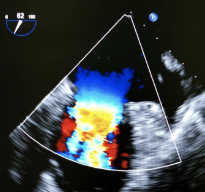

The Premium Screening is Executive Health’s most extensive medical examination - offering a full overview of your health in just one visit.Through high-resolution MRI imaging, advanced laboratory analysis and specialist consultation, we detect potential risks before symptoms appear. Our experienced physicians provide clear answers and personal guidance, helping you stay healthy, informed and in control.

3–5% of our clients uncovered a potentially life-threatening health condition during their visit. Because these findings are made early, we are able to address and reverse the conditions before they become serious.

30–40% are diagnosed with previously unknown relevant findings.